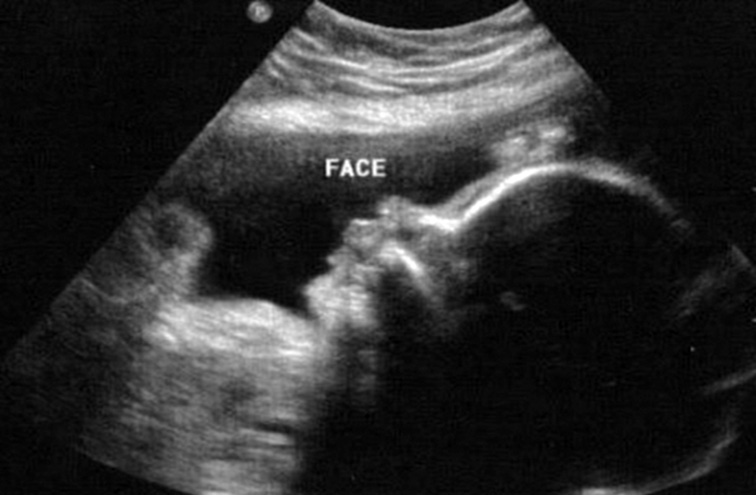

На полученных сонограммах у 15 беременных визуализировались все 20 зубных зачатков. Лицо плода помещалось на экран таким образом, чтобы можно было вывести профиль, а сдвиг и вращение изображения давали возможность осмотра верхней и нижней челюсти (рис. 8, 9). У трех беременных визуализация была затруднена. С использованием плоскостей сканирования, оптимизированных для исследования конкретного органа, осуществлялась визуализация нижней челюсти целиком, включая сочленение с верхней челюстью.

Рис. 8. Лицо плода / Fig. 8. Fetal face

Рис. 9. Зубные зачатки / Fig. 9. Dental rudiments